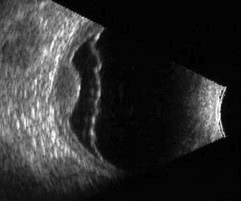

CURSO DE ECOGRAFÍA OCULAR

Un miembro del equipo de oftalmólogos del Instituto de Oftalmología de Toledo, la Dra. Eva Mª Hernández, ha asistido al Curso de Ecografía Ocular – Curso Acreditado como Formación Continuada- celebrado el día 19 de septiembre de 2013 en el Colegio de Médicos de Madrid.